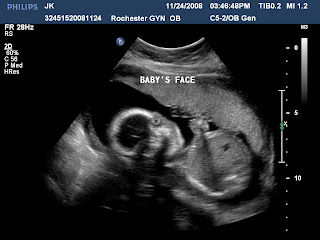

Here are a few pictures of our sweet baby at 20 weeks...